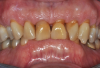

Fig 2. Pretreatment views: right lateral (Fig 2), frontal (Fig 3), and left lateral (Fig 4). Note: The maxillary right first molar (tooth No. 3) (Fig 2) would be identified as the most periodontally involved molar that was planned to be maintained.

Figure 2

Fig 3. Pretreatment views: right lateral (Fig 2), frontal (Fig 3), and left lateral (Fig 4). Note: The maxillary right first molar (tooth No. 3) (Fig 2) would be identified as the most periodontally involved molar that was planned to be maintained.

Periodontal examination revealed generalized BOP and PDs up to 9 mm in the maxillary and mandibular molars with multiple furcations in each molar (Figure 2 through Figure 7). He presented with class I mobility in many posterior teeth and class II mobility in teeth Nos. 3 and 9 (maxillary right first molar and maxillary left central incisor, respectively). The periodontist decided to score tooth No. 3 for the PRS, as this was the most periodontally involved molar that was planned to be treated and maintained (Figure 2 and Figure 8). This tooth (maxillary right first molar = score 1) presented with probing depths of 7 mm (score 1); three total furcation invasions (score 3) (mesial [degree II furcation], buccal [degree I furcation], and distal [degree II furcation]); and a class II mobility (score 2). The total PRS for tooth No. 3 was 8, representing a "guarded" prognosis. Based on this score, the likelihood of not losing any teeth to periodontal disease for 15 years was 81%, and for 30 years the likelihood was just 56% (Figure 9).7